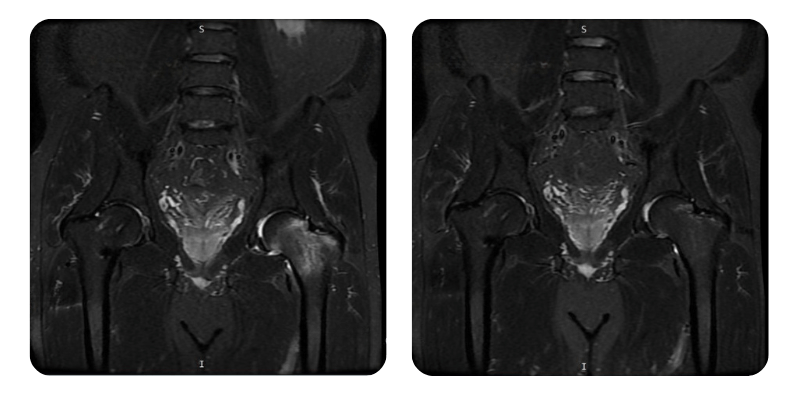

Prima

Dopo

B.A.M., 56 anni - Necrosi avascolare della testa e del collo femorale sinistro post-frattura del collo femorale destro

Diagnosi: Necrosi avascolare della testa e del collo femorale sinistro post-frattura del collo femorale destro.

Evoluzione: Dopo 20 sedute di ossigenoterapia iperbarica, il paziente presenta una remissione di circa il 90%, con scomparsa completa della sintomatologia lombare e dell'anca. La mobilità è migliorata in modo significativo, senza dolore notturno e senza necessità di interventi aggiuntivi.